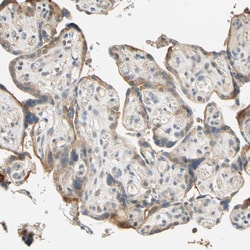

Immunogen sequence: FQSNRMDDQR CCLQEKNCHT ASTTTSSTPP KMMLKTSSVP VVSPNTDEFL DLLASSQSRR LDDQRASFSN LPGLRLTQNS QSVLSHLMTN DNKEADEDFF D Highest antigen sequence identity to the following orthologs: Mouse - 78%, Rat - 75%.

The protein encoded by this gene belongs to a family of proteins that modulate activation of G proteins, which transduce extracellular signals received by cell surface receptors into integrated cellular responses. The N-terminal half of this protein contains 10 copies of leu-gly-asn repeat, and the C-terminal half contains 4 GoLoco motifs, which are involved in guanine nucleotide exchange. This protein may play a role in neuroblast division and in the development of normal hearing. Mutations in this gene are associated with autosomal recessive nonsyndromic deafness.

| Applications | Immunohistochemistry (Paraffin), Western Blot |